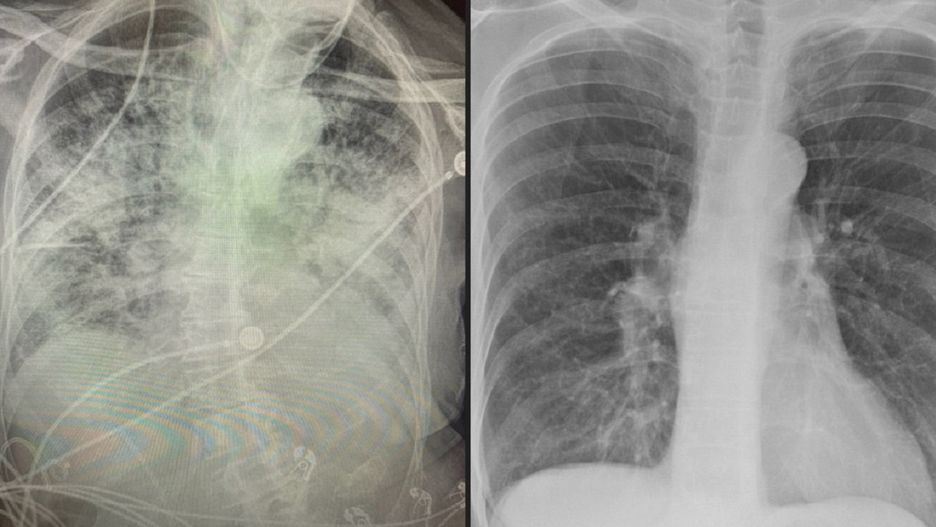

płuca.Po lewej płuca pacjenta z Covid-19, a po prawej nałogowego palacza.

Dr Brittany Bankhead-Kendall, chirurg z Teksasu, pokazała trzy zdjęcia rentgenowskie płuc: zdrowego pacjenta, palacza i pacjenta z Covid-19. W najgorszym stanie były płuca osoby zakażonej - mętne, pełne płynów i uszkodzeń.

Lekarka zauważyła, że płuca osoby palącej są zamglone, jednak osoby chorej na Covid-19 całkowicie białe. To oznaka, że w środku znajdują się płyny i liczne uszkodzenia. Pacjent nie jest w stanie przez to przyjąć większej ilości tlenu.

Nie wiem, kto musi to usłyszeć, ale płuca "po Covid-19" wyglądają gorzej niż jakiekolwiek płuca nałogowego palacza, które kiedykolwiek widzieliśmy - napisała na Twitterze lekarka.

Lekarka powiedziała, że każdy jej pacjent z Covid-19 miał prześwietlenie płuc. U 70-80 proc. z nich zauważono różne uszkodzenia płuc. Wielu z nich nie miało silnych objawów zakażenia i nie skarżyło się na problemy z oddychaniem czy duszności.